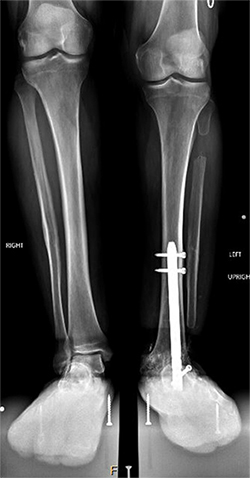

Guy Natale X-ray before leg lengthening. Notice the difference in the level of the knees.

Guy Natale, MD, a general practitioner in Arcadia, had a left leg that was 2 inches shorter than his right.

Natale wasn’t born with a shorter leg. Ankle injuries over years of playing football, baseball and racquetball led to his left ankle being fused at age 51. The resulting discrepancy in the length of his legs led to scoliosis and severe back pain. At age 71, he had five vertebrae fused. The operation helped with his back pain but made the difference in the lengths of his legs even worse.

The operation took place in November 2022. Because Natale’s ankle was fused, Marecek chose to lengthen Natale’s tibia, or shin bone, rather than his femur. Marecek also identified that Natale’s ankle had been fused out of alignment. So, first he corrected the ankle’s alignment, then he broke Natale’s tibia and inserted a distraction rod—the kind that could push the two sides of the broken bone apart.